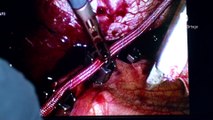

Le docteur Saja Scherer explique la technique de décompression des nerfs autour de la tête, visant à soulager certaines céphalées chroniques. C’est la seule patricienne, avec son collègue de la Clinique de la Source Giorgio Pietramaggiori, à effectuer ce genre d’intervention chirurgicale en Suisse, l’une des rares en Europe.